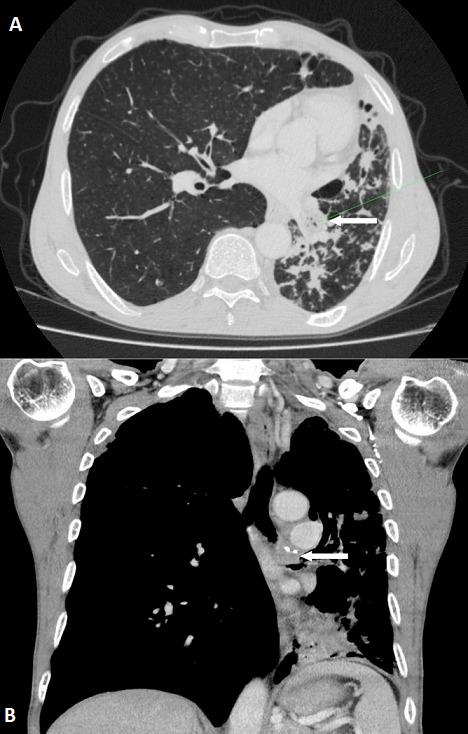

Adenoid cystic carcinoma (ACC) is a rare malignant epithelial tumor that predominantly originates in the salivary glands. Primary ACC of the tracheobronchial tree is extremely rare. We report two new cases of central airways primary ACC: a 58 year-old male with an ACC of the left main bronchus who underwent a pneumonectomy with node dissection, and a 52 year-old female with proximal tracheal ACC presenting as asthma treated by surgical resection and a postoperative radiotherapy. Primary ACC of the tracheobronchial tree is often misdiagnosed given the non-specific clinical presentation. An early diagnosis is essential to ensure good outcomes. An interdisciplinary treatment is required based especially on surgery and radiotherapy.

腺样囊性癌(ACC)是一种罕见的恶性上皮肿瘤,主要起源于唾液腺。原发性气管支气管树 ACC 极为罕见。我们报告两例中央气道原发性 ACC 新病例:1 例 58 岁男性,左主支气管 ACC 行肺切除术及淋巴结清扫术;1 例 52 岁女性,近段气管 ACC 表现为哮喘,行手术切除和术后放疗。由于非特异性临床表现,原发性气管支气管树 ACC 常被误诊。早期诊断对于确保良好的预后至关重要。需要根据手术和放疗等方法进行跨学科治疗。